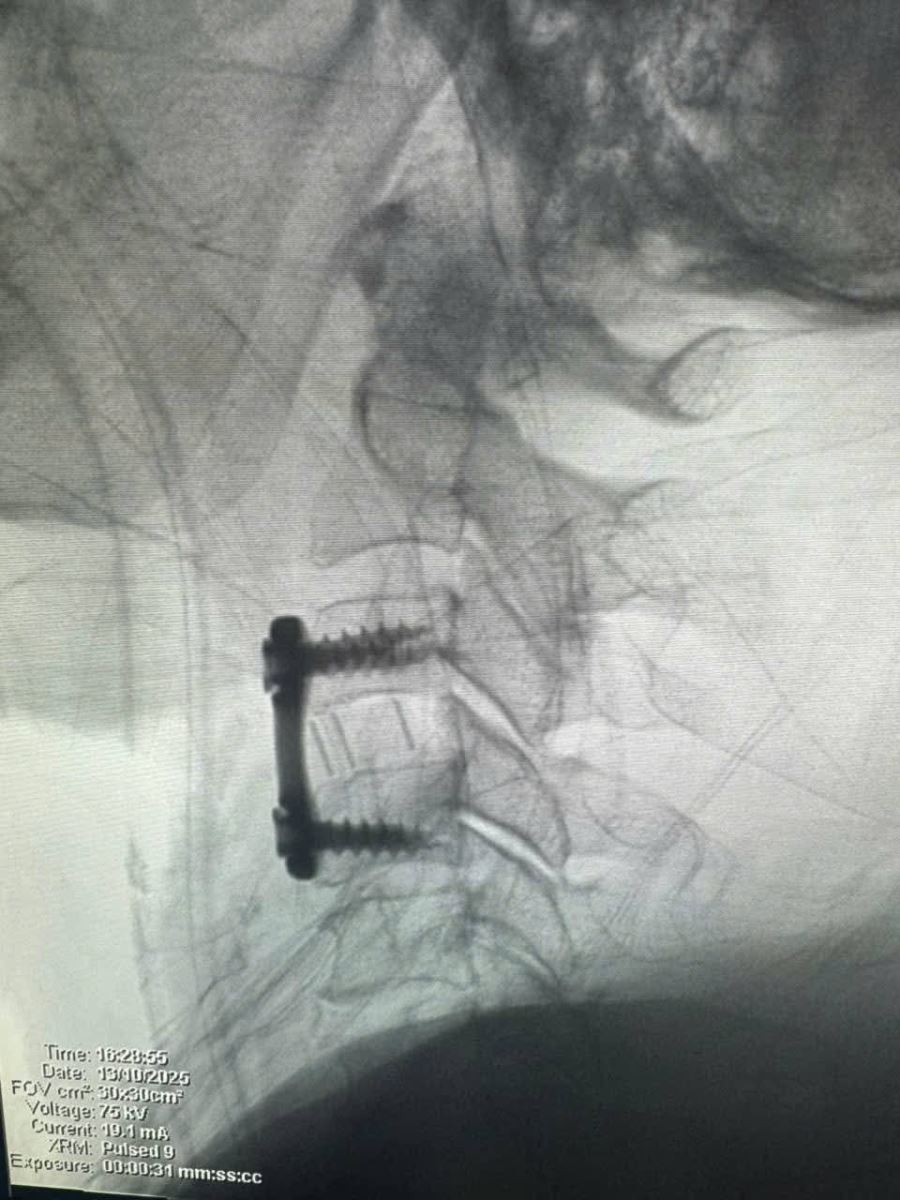

Bệnh nhân được phẫu thuật ACDF C3–C4 (lấy nhân đĩa đệm thoát vị, giải phóng chèn ép tủy – rễ thần kinh, hàn xương và cố định cột sống cổ lối trước).

Sau mổ: tê bì hai tay giảm rõ rệt, cơ lực cải thiện, tình trạng thần kinh ổn định.